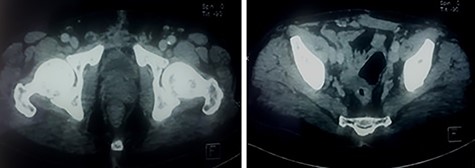

The patient was seen on Day 15, 1 month, 3 months, 9 months postoperatively. The control CT scans made at 3 and 9 months postoperatively had shown no abnormalities without any residual mass (Fig. 6).

Control CT scan at 9 months postoperatively: the bladder and prostate are normal in appearance and there is no residual mass.